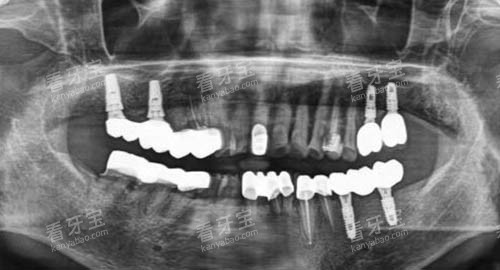

在设备设施上,昆大口腔紧跟国内外口腔医学发展趋势,引进了一系列可靠的口腔诊疗设备。

例如,智能化口腔全景机能够快速、比较准地获取口腔内部的详细影像,为医生的诊断提供精密的数据支持;可靠的种植牙系统,大大提高了种植牙的可行性和稳定性。